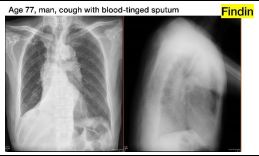

7.CC: cough for one year and back pain